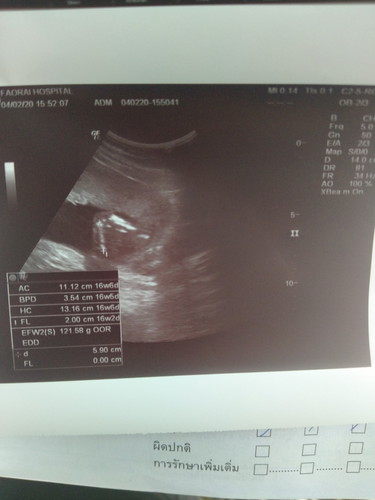

ช่วยดูหน่อยได้ไหมค่ะ

ว่า ผู้หญิงหรือผู้ชาย

อายุครรภ์เท่านี้ยังบอกเพศไม่ได้จ๊ะ อวัยวะยังไม่โตพอ

มันไม่ชัดเลยคะแม่